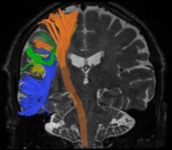

The one-year program provides advanced training in all neuroimaging modalities including advanced imaging techniques, such as CT and MR perfusion, MR spectroscopy, CSF flow imaging, diffusion tractography, and functional MRI. Fellows will also be exposed to advanced nuclear medicine techniques by way of multidisciplinary conferences, including brain PET with various clinical and investigation radiotracers due to the availability of an advanced cyclotron and integrated PET/MR. The close clinical and research relationship with various clinical departments results in exposure to the most advanced neuroimaging techniques in epilepsy, brain tumors, and neurodegenerative disease, amongst others. The program is a well-rounded and varied experience that can serve as a solid foundation for either academic or private practice careers.

A dedicated on-site 3D lab handles data processing for numerous modalities, including brain perfusion studies, CT angiography, dual energy CT, spectroscopy, MEG, and functional MRI.

In addition to teaching at the workstation, dedicated neuroradiology lecture sessions are held throughout the week for the fellows and residents on rotation. Additional teaching sessions cover advanced neuroimaging techniques, such as fMRI, Diffusion Imaging, Perfusion, and CSF flow imaging. Fellows will also have the opportunity to participate in interpreting functional cases.